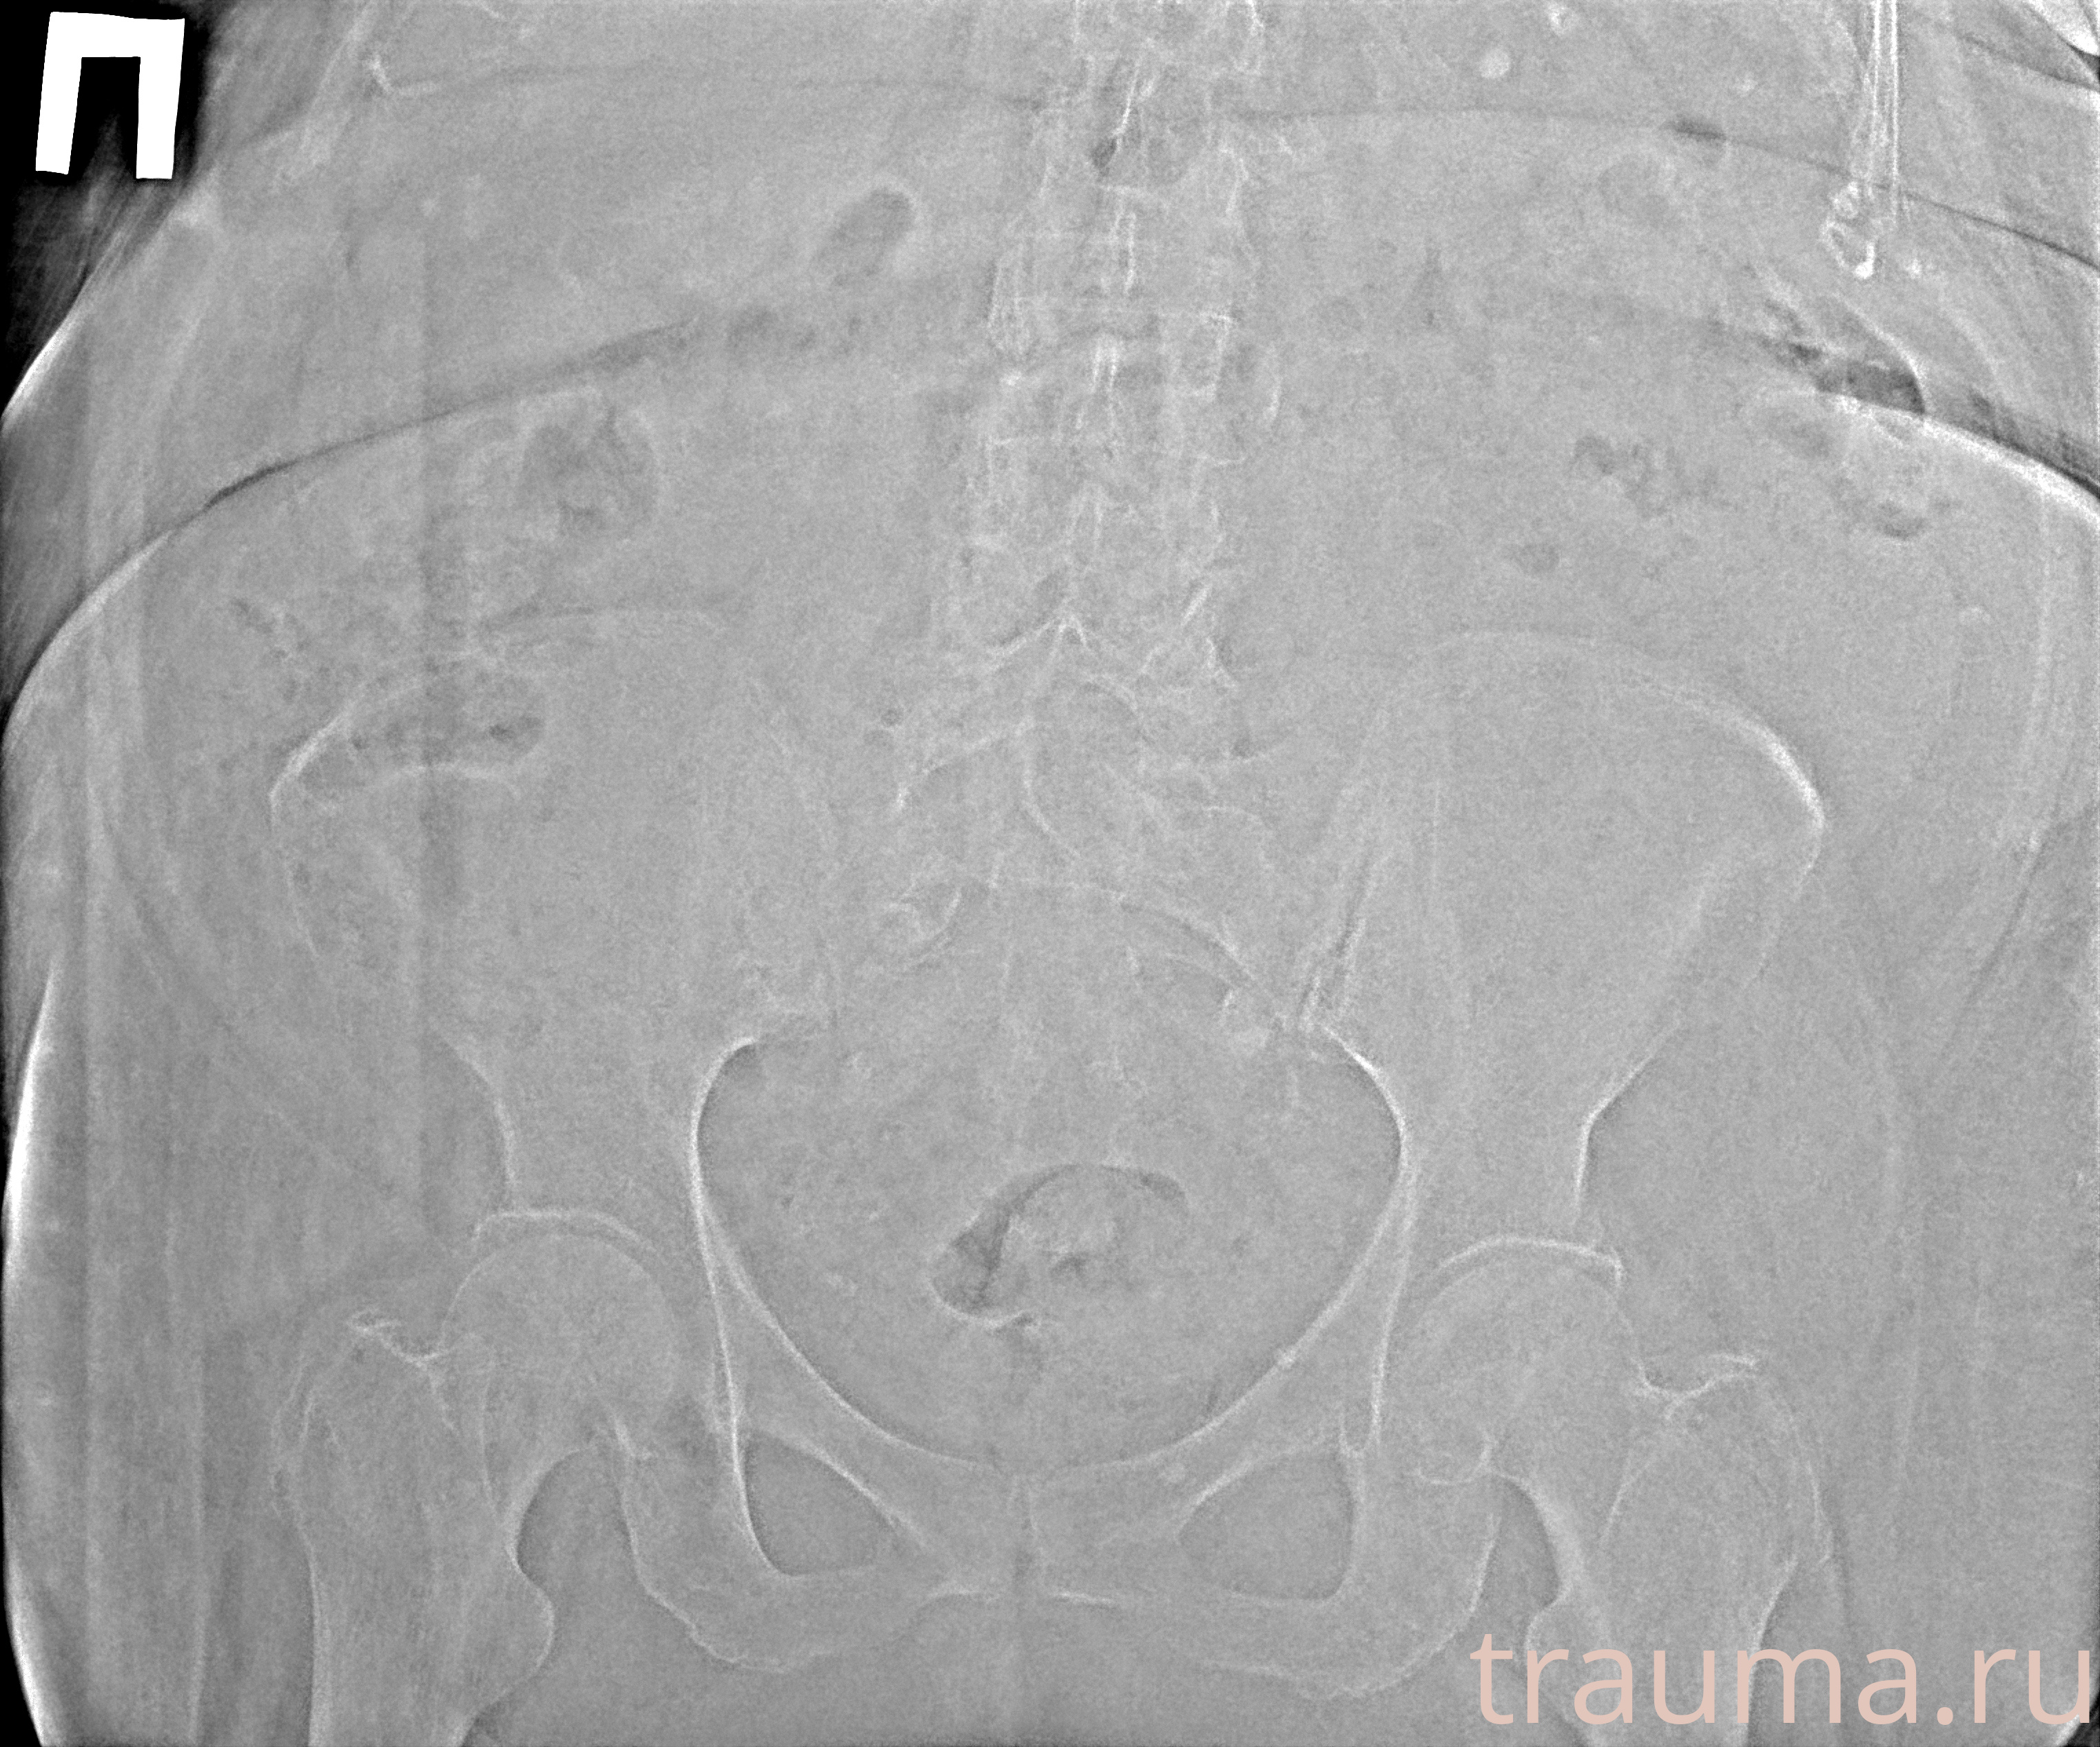

Рентген на дому: по вашему адресу приезжает врач-рентгенолог, травматолог-ортопед с мобильным рентгеновским аппаратом, проводит диагностику травмы или заболевания, делает необходимые рентгенограммы, дает рекомендации по дальнейшему лечению. Получить качественные снимки в домашних условиях возможно благодаря уникальной методике, разработанной МосРентген Центром для института  Склифосовского